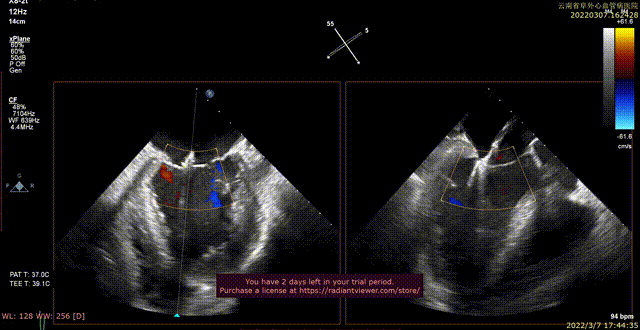

术前xPlane view提示:二尖瓣重度反流

术后xPlane view提示:二尖瓣反流显著减少